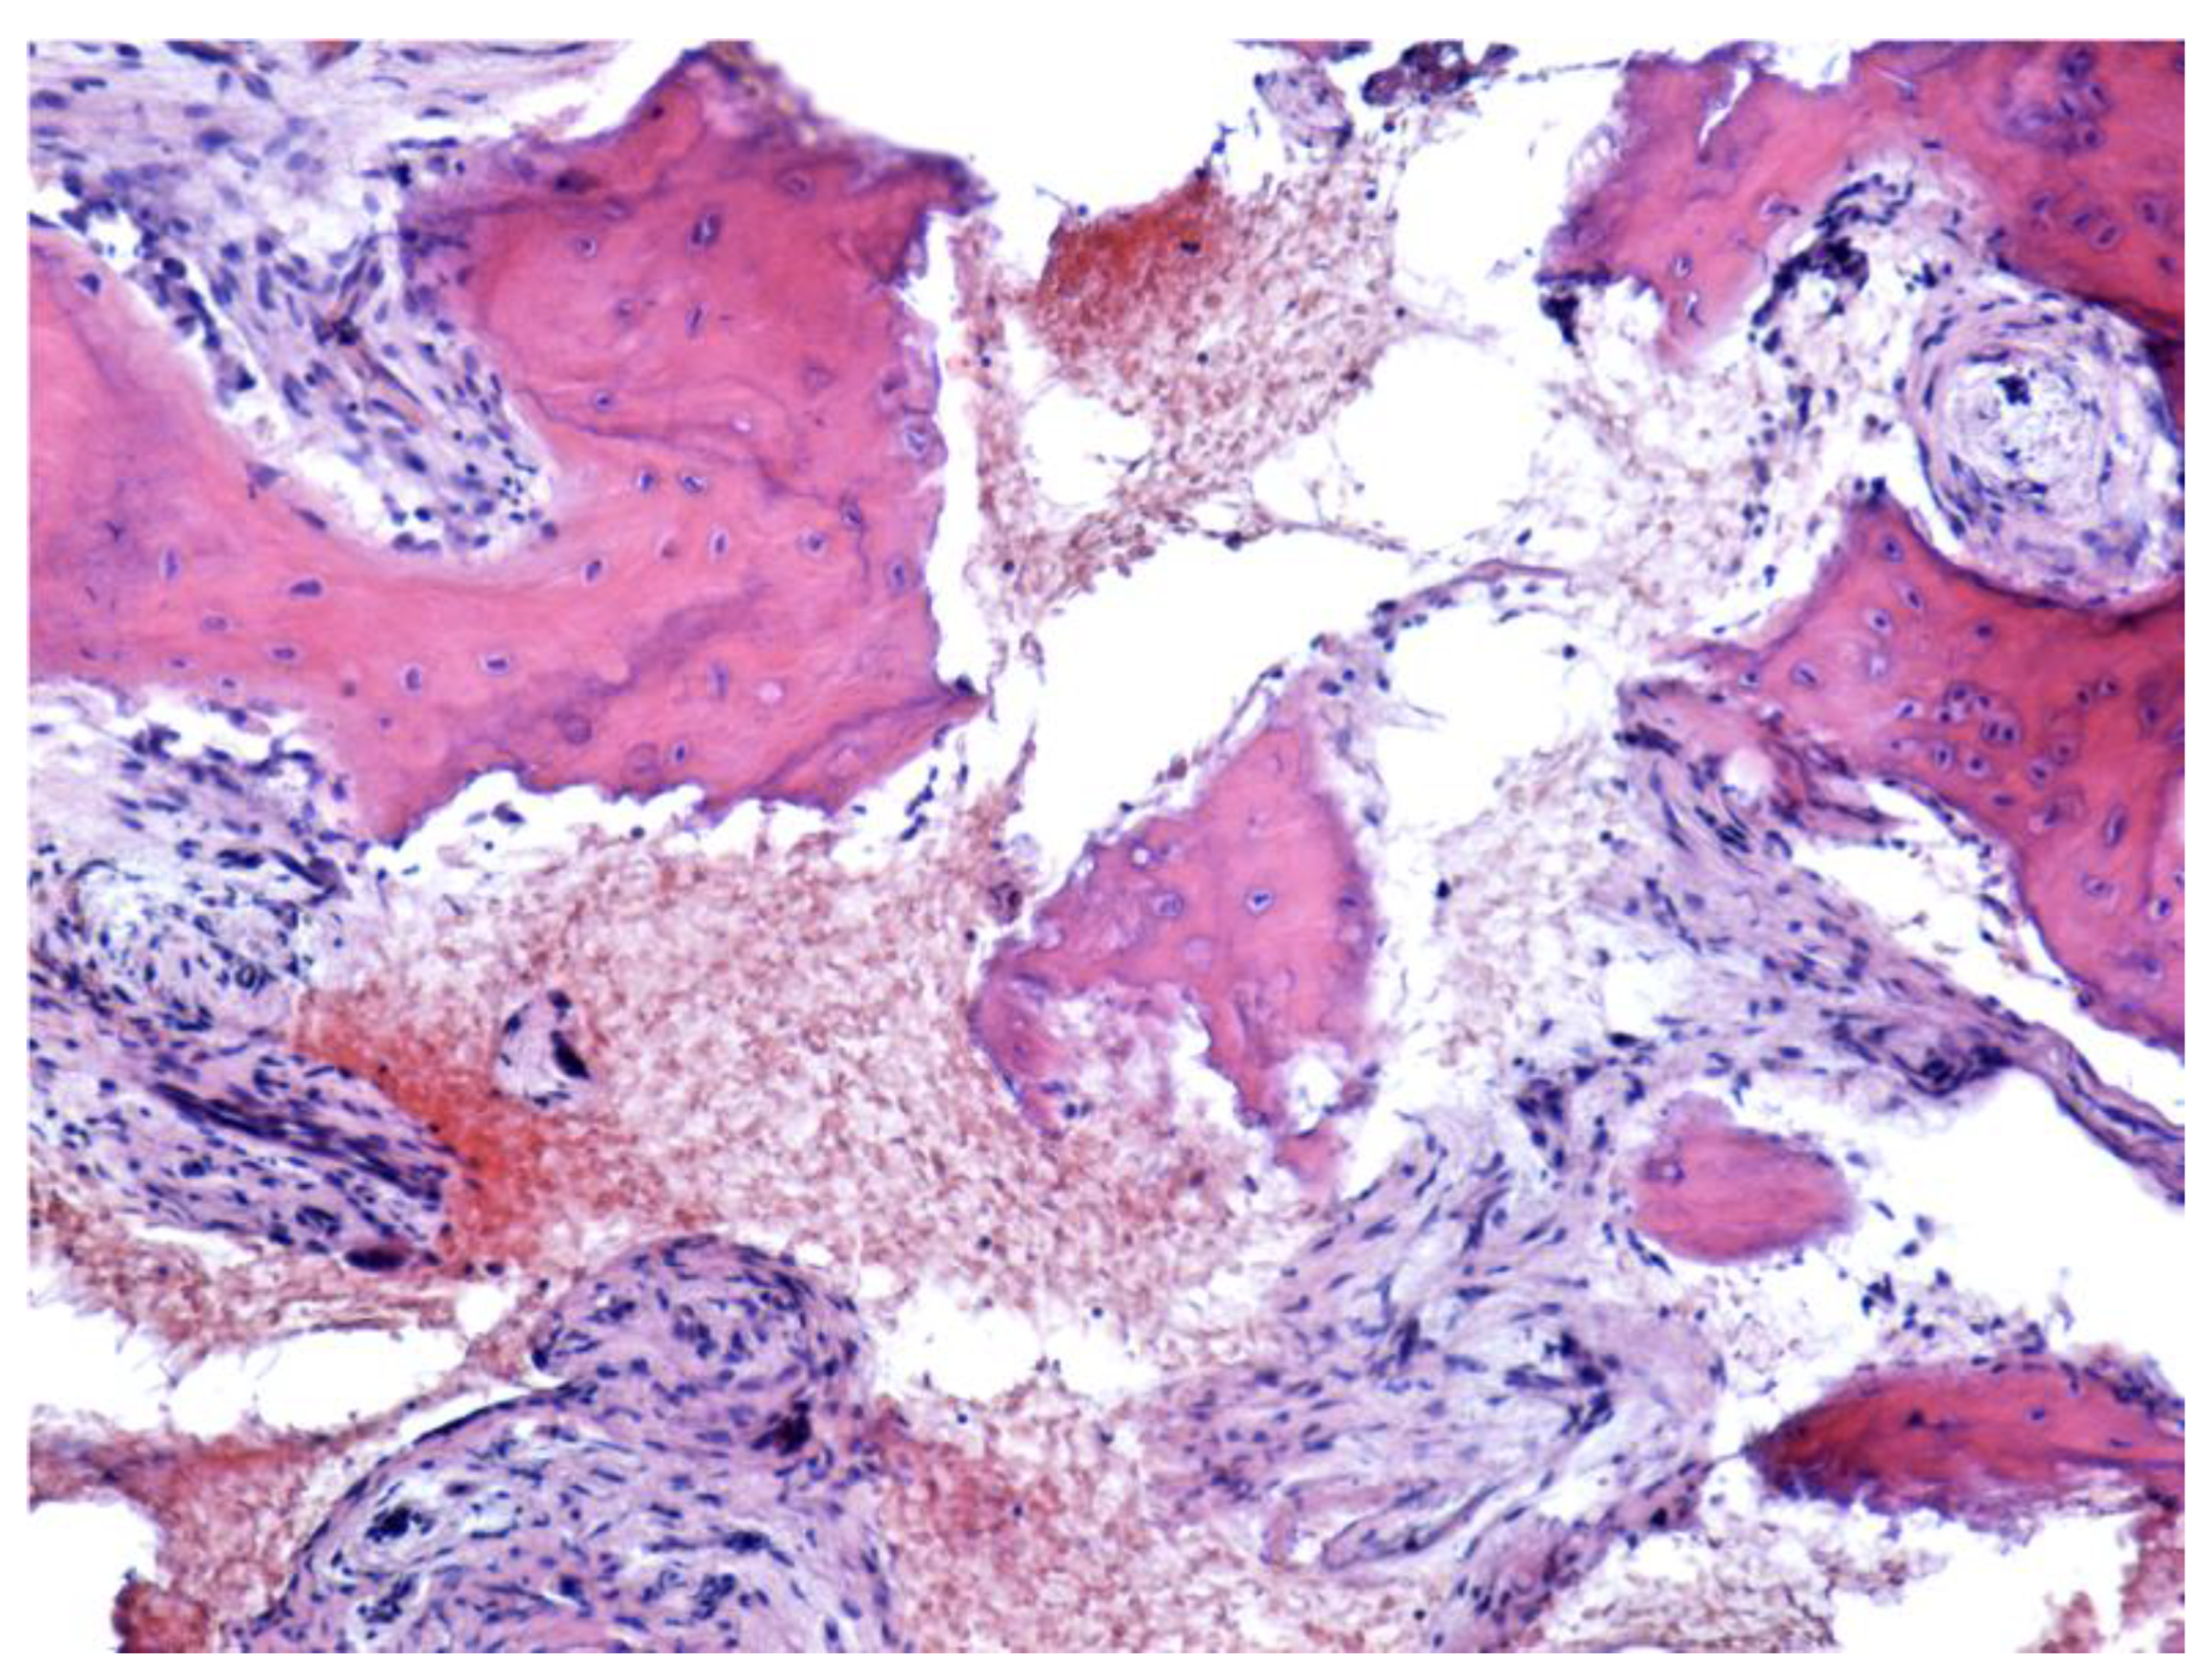

- Favia, G.; Pilolli, G.P.; Maiorano, E. Histologic and histomorphometric features of bisphosphonate-related osteonecrosis of the jaws: An analysis of 31 cases with confocal laser scanning microscopy. Bone 2009, 45, 406–413. [Google Scholar] [CrossRef] [PubMed]